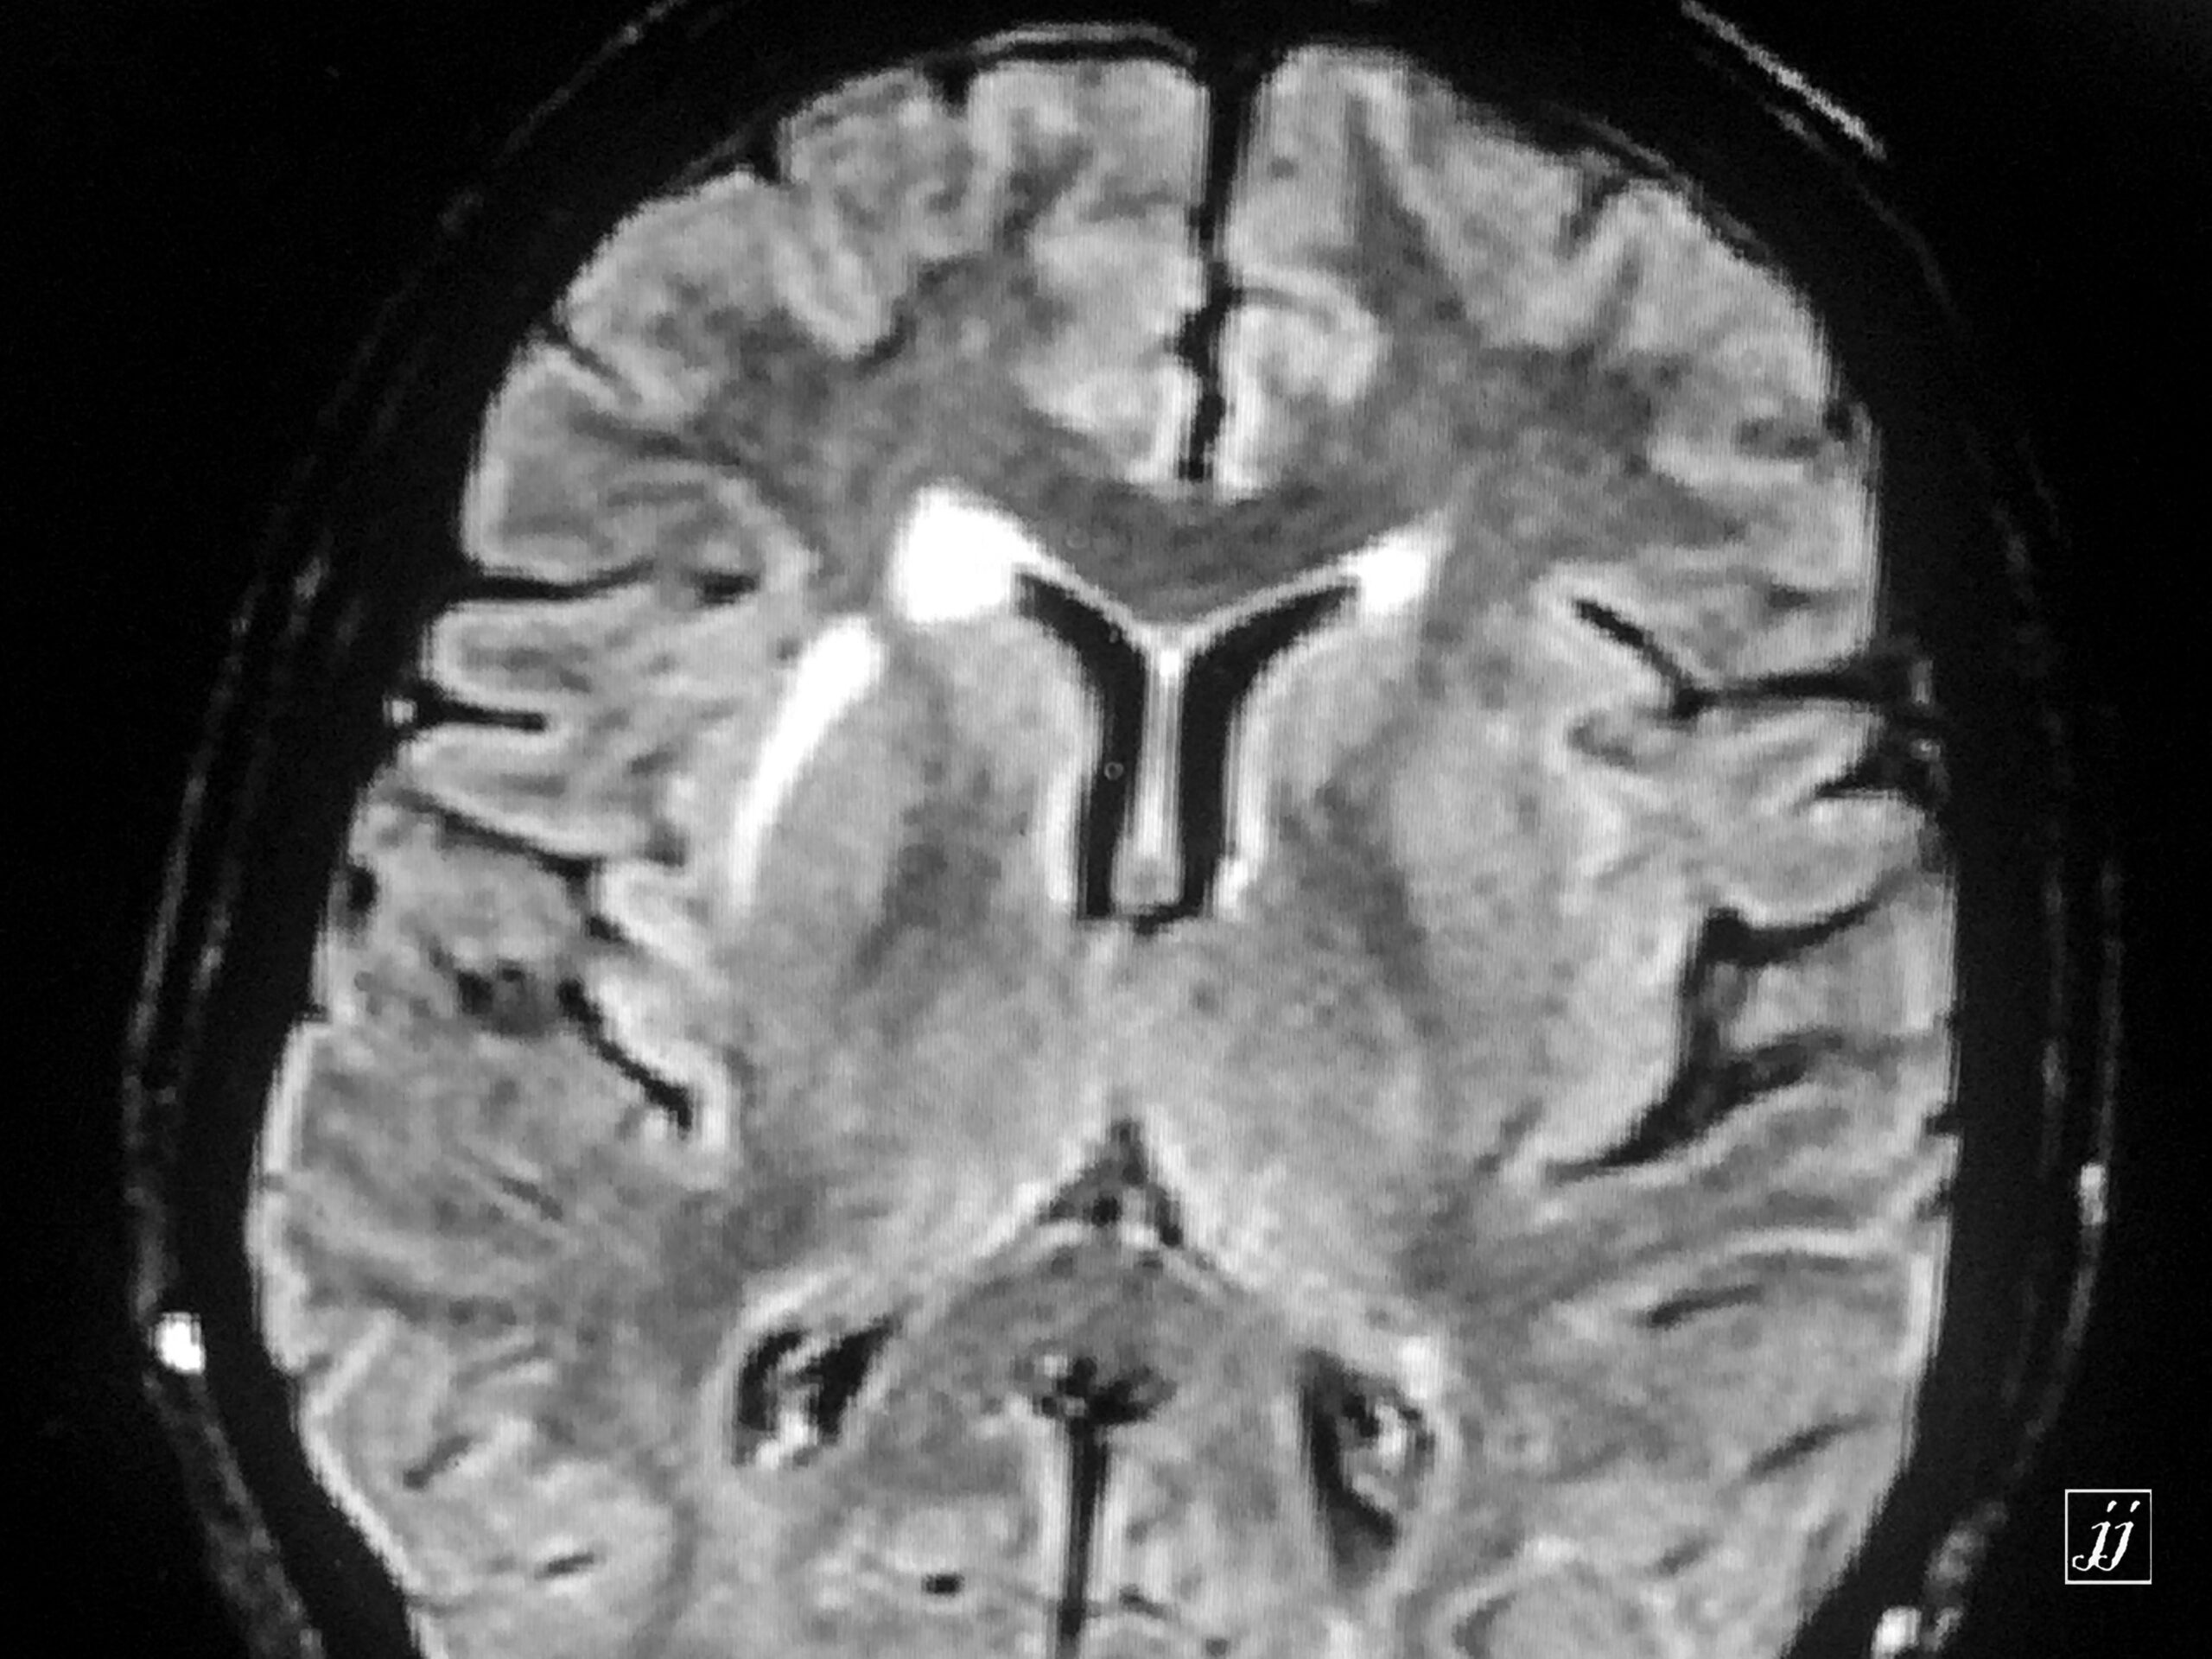

Brain- insular ischemic change (1)